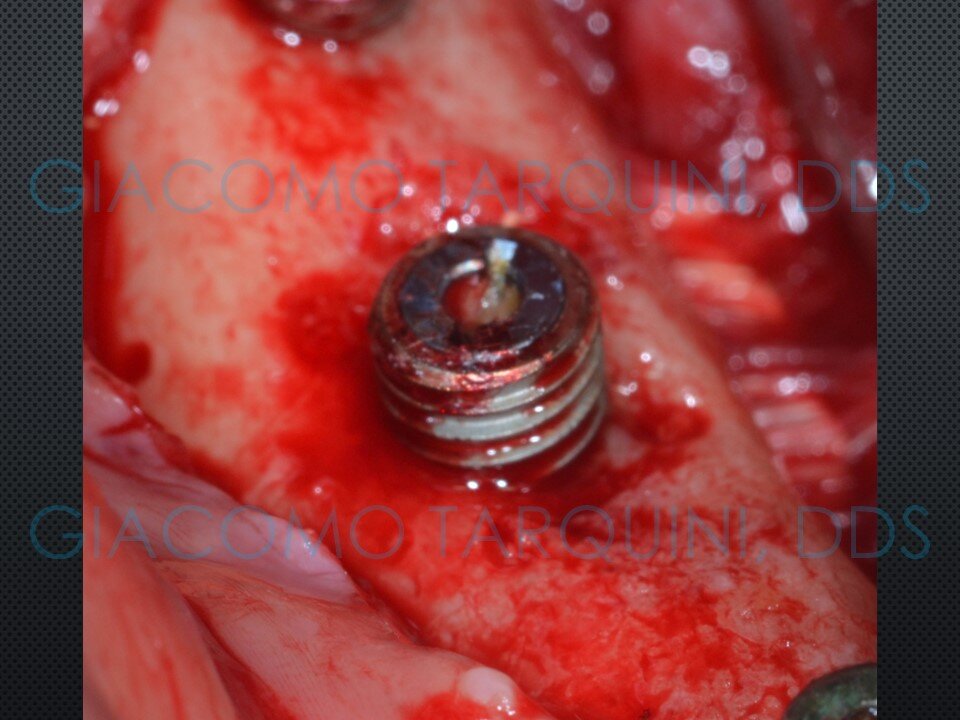

CASO CLINICO

Il caso clinico illustra il trattamento chirurgico-rigenerativo di un impianto endosseo affetto da peri-implantite effettuato secondo il protocollo «PIEZOCLEAN by Dr. Giacomo Tarquini»